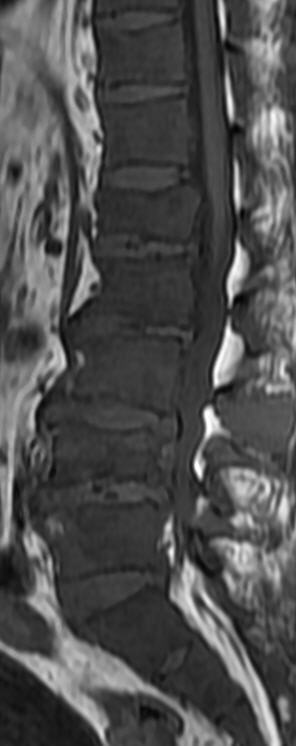

MRI

可提供腰椎管的矢状面、冠状面和轴位横断面上的影像。椎管狭窄以T2加权像显示较好,脑脊液为高信号,产生所谓“脊髓造影”的效果,而骨质增生,骨赘、间盘均为低信号,能清晰地显示椎管狭窄,以及对脊髓的压迫情况。但对肥大的黄韧带、骨质增生等的判断则不如较高清晰度CT扫描。

腰椎正常MRI解剖。

腰椎管狭窄MRI表现。